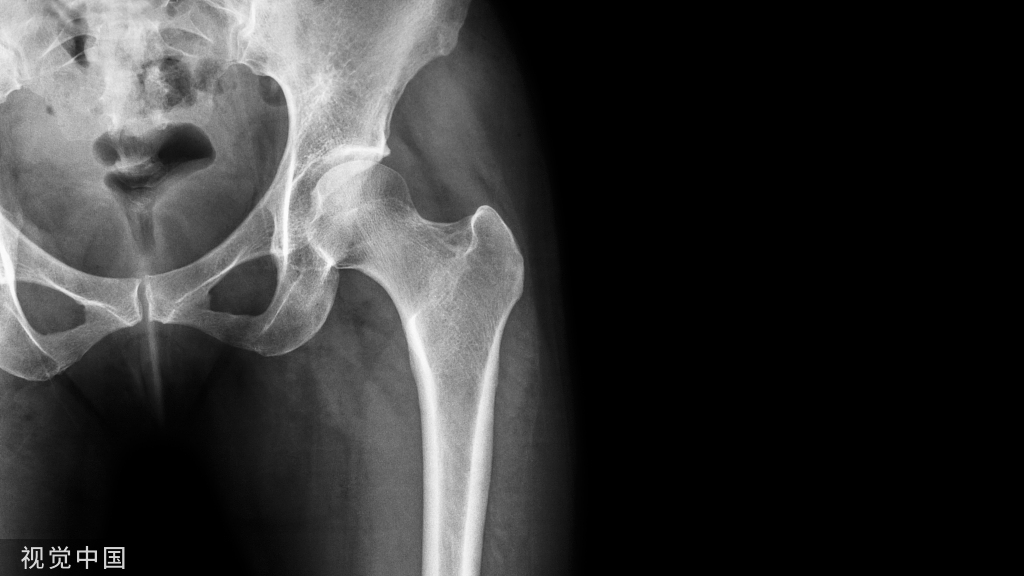

患者是30多岁的年轻男子,红色标记那颗牙松动,要求拔牙,开始嫌麻烦不愿拍片,后来经过再三劝说还是拍了片。结果把所有人包括他自己都吓了一跳。估计是良性,具体还得去医院住院手术做病理检查,所以大家不要忽视一张片子带来辅助检查的重要性。

试想,如果没有拍片,直接贸然拔牙,一旦出现问题......一张牙片,“救”了诊所,也救了患者!